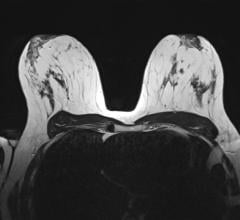

Breast density, or fibroglandular density, is found through breast imaging and compares the amount of fat to the amount of tissue.